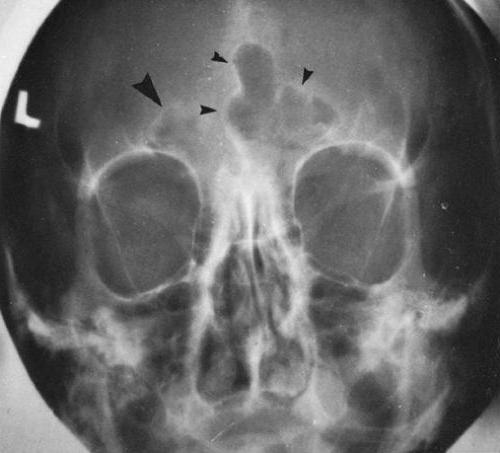

- Рентгеноскопия. Этот метод применяется наиболее часто. С помощью рентгенодиагностики врач определяет форму и состояние лобных пазух, выявляет воспаление, отечность, определяет характер содержимого.

При постукивании можно определить местонахождение боли, а анализ крови позволяет выявить инфекционное или аллергическое воспаление. Для получения окончательной информации по диагностике воспалительных процессов в лобных, гайморовых и других полостях требуется проведение дополнительных инструментальных исследований. Сюда входят диафаноскопия, рентгенография, компьютерная томография и УЗИ.

- Исследование при помощи рентгеновских лучей. Рентгеновский метод помогает определить увеличение размеров пазухи, структуру перегородки в данном органе и четкость её контуров.